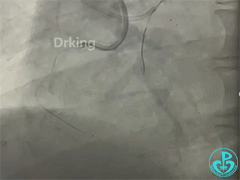

右冠造影:

导丝怎么扩收藏:器械难以通过的CTO病变之技术图谱_https://www.jmylbn.com_新闻资讯_第6张

导丝怎么扩收藏:器械难以通过的CTO病变之技术图谱_https://www.jmylbn.com_新闻资讯_第7张

导丝怎么扩收藏:器械难以通过的CTO病变之技术图谱_https://www.jmylbn.com_新闻资讯_第8张